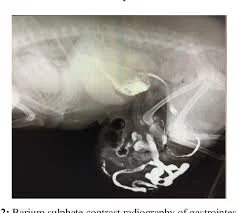

barium series

Imaging

Depending on the case, a vet may recommend:

• Ultrasound to visualize organs inside the hernia

• X‑rays to assess abdominal structures

• Bloodwork to evaluate overall health before surgery

These tools help determine whether the hernia is reducible (able to be pushed back in) or incarcerated (trapped).